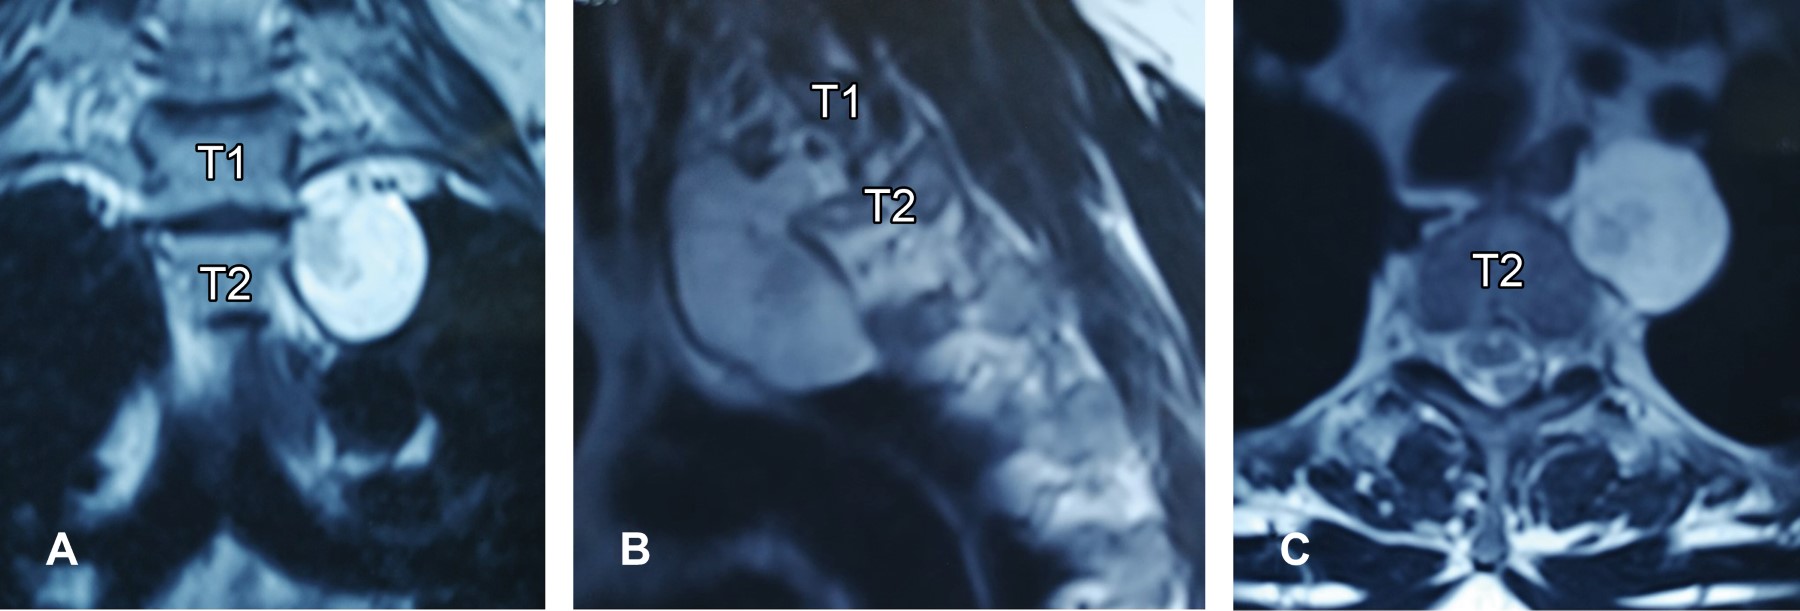

Masculino de 45 años acude por cervicalgia de tres meses; en resonancia de columna cervical se encontró incidentalmente tejido neoplásico de 8 × 4 cm paravertebral izquierdo a nivel de T1-T2 (Figura 1). Por toracotomía, con microscopio, se practica resección total de la lesión (Figura 2); histopatológicamente correspondió a cordoma, la inmunohistoquímica: EMA, CK8, S-100 positivos en células fisalíferas y brachyury positivo en el núcleo de células neoplásicas (Figura 3). A un año de seguimiento, paciente asintomático con resonancia normal.

Figura 1